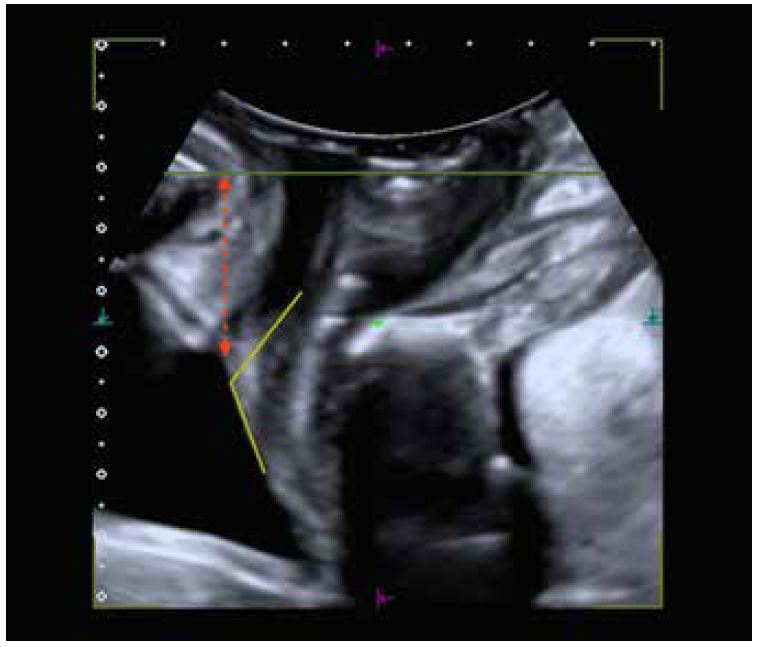

Основні заходи, які використовуються для оцінки гіпермобільності уретри:

• Відстань між шийкою сечового міхура і лобковим симфізом: вертикальна відстань (пунктирна червона лінія на мал. 4) між шийкою сечового міхура та уявною горизонтальною лінією (зелена лінія на мал. 4), що проходить повз задньонижній край лобкового симфізу (мал. 4). Це найбільш аналізований і відтворюваний параметр для оцінки рухливості уретри у пацієнтів із SUI. Тим не менш, важко встановити точку відліку для діагностики SUI, тому його необхідно вивчати з урахуванням клінічного контексту пацієнта.

• Ретровезикальний або задній уретровезикальний кут: кут, визначений між проксимальною віссю уретри та найближчою до уретри частиною задньої стінки сечового міхура (жовті лінії на мал. 4). Цей параметр також не має визначеної граничної точки для визначення SUI, однак це корисно для діагностики пролапсу тазових органів (POP) переднього відділу.

Інші критерії, що використовуються для діагностики SUI:

• Воронкоподібність шийки сечового міхура: полягає у відкритті шийки сечового міхура під час навантаження. Це може свідчити про можливу внутрішню етіологію: сфінктер уретри як причина SUI

Малюнок 4. Він включає відстань між шийкою сечового міхура і лобковим симфізом (червоний колір) і ретровезикальний кут (жовтий).